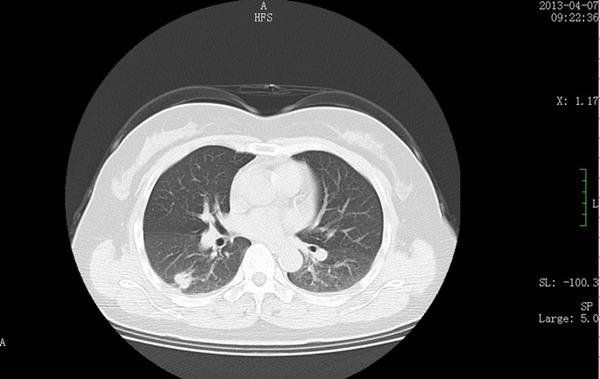

CT示右肺下叶结节(肺窗)